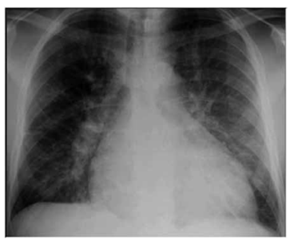

Paciente do sexo masculino, 57 anos de idade, acompanhado pela esposa, procurou serviço de urgência por dispneia aos pequenos esforços, edema de membros inferiores,

diminuição do volume urinário, tosse seca associada a dispneia progressiva. Os sintomas se iniciaram há, aproximadamente, 6 meses, com dispneia seguida de edema. A dispneia,

que era aos esforços moderados, rapidamente progrediu até

estar presente no repouso. À ausculta pulmonar apresentou

roncos e estertores em bases pulmonares. Ao raio X apresentou a radiografia a seguir:

(Arquivo pessoal, imagem usada com autorização)